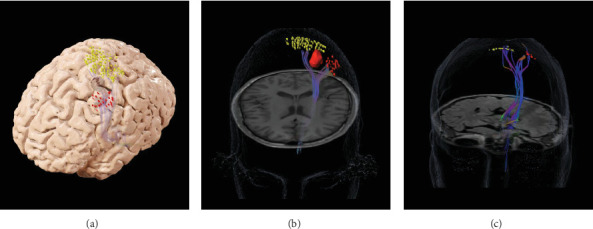

Background: Tumors infiltrating the precentral gyrus remain a unique operative challenge. In this study, we explored a novel approach for awake craniotomy involving a patient playing a drum pad during resection of low-grade glioma, with the use of preoperative navigated transcranial magnetic stimulation (nTMS)-generated diffusion tensor imaging (DTI) and high-density real-time electrocorticography (ECoG). Observation: A 36-year-old left-handed male with a low-grade glioma in the left hemisphere hand knob region had a grand mal seizure. We combined preoperative nTMS-DTI with intraoperative passive functional mapping using high-density real-time ECoG. During an awake craniotomy, the patient played a drum pad while we assessed somatosensory-evoked potentials (SSEPs) using a 64-channel ECoG grid. This confirmed the absence of motor-evoked potentials (MEPs) over the tumor area, consistent with nTMS findings. Continuous monitoring of the patient's drum pad performance during the resection allowed for a gross total resection (GTR) of the tumor. Following the resection, he experienced some weakness in the intrinsic muscles of his right hand, which returned to full normal function at 6 months. At the end of 1 year, he remained seizure-free. Conclusion: A multimodal mapping strategy combined with awake monitoring of drum playing enabled preservation of function while achieving GTR in a patient with a motor-eloquent glioma.

Abstract Image